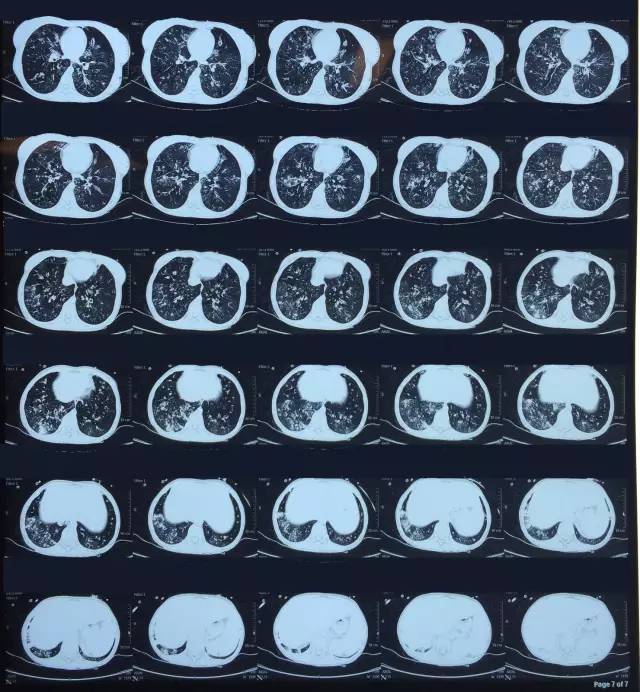

肺CT見下圖

該患者肺部影像學(xué)表現(xiàn)為明顯的支氣管擴(kuò)張,同時(shí)伴有彌漫的滲出斑片影,考慮合并感染,細(xì)菌學(xué)培養(yǎng)提示為綠膿桿菌,結(jié)合藥敏結(jié)果給予頭孢他啶+阿米卡星抗感染,患者存在II型呼吸衰竭予氣管插管機(jī)械通氣支持,加強(qiáng)體位引流排痰,治療18天,患者情況好轉(zhuǎn)出院。